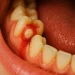

牙齒變黑的原因5:牙齒疾病

你最擔心嗰個——蛀牙——確實會令牙齒變黑。但唔少人忽略咗:牙周病、牙齦出血、牙根暴露、舊補牙邊緣滲漏,都可以令局部變黑。蛀牙早期未必痛;到你「一下痛一下唔痛」先嚟處理,有時已經入深層。若黑色位置伴隨敏感、咬合痛、食物塞住、或者牙肉腫痛,就唔好拖。